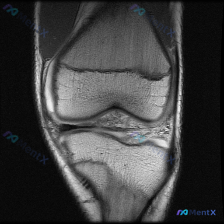

今天遇到一个挺有代表性的病例,主诉提示膝关节半月板异常,只提供了单张膝盖MRI冠状位T1加权像,整理一下分析思路跟大家分享。 一、病例核心信息 核心问题:患者主诉提示半月板异常,仅提供单一层面冠状位T1加权MRI读片 影像观察结果: 1. 骨骼:股骨远端、胫骨近端骨皮质完整连续,骨髓腔T1信号为均匀...

看到这张膝关节MRI的读片请求,目标是找半月板异常,但整理完全片发现这个病例的陷阱挺典型,分享出来给大家参考。 一、病例影像基本信息 这是一张膝关节冠状位T1加权磁共振图像,只有单一层面单序列,我们先按结构捋一遍所见: 1. 骨骼结构:股骨远端、胫骨近端骨皮质连续,没有明显骨折线;但整个骨髓腔在T1...

看到这个病例挺有代表性的:临床怀疑半月板异常,但提供的只有单张膝关节MRI冠状位T1加权序列,读片下来居然没发现明确异常,整理一下我的分析思路给大家参考。 先整理病例影像核心信息 这是膝关节MRI冠状位T1加权序列,我们先明确序列特点:T1加权主要看解剖结构,脂肪/骨髓是高/中高信号,液体、皮质骨、...